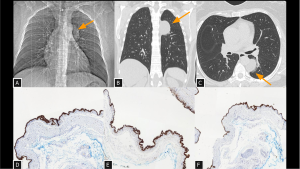

Fig 17: Case 18 – Tuberculous spondylodiscitis:

Panels A, B, and C: Sequelae of tuberculosis are indicated by fibroatelectatic streaks and irregular pulmonary nodules in the lung apices (A). Lytic lesions are seen in the vertebral bodies (T6–T12) (B). In addition, there are heterogeneous paravertebral collections adjacent to the affected vertebral bodies (C), representing an important differential diagnosis for paravertebral mediastinal masses.

SYSTEMATIC APPROACH: 1. Age: Any. | 2. Morphology: Vertebral destruction with soft tissue component (cold abscess). | 3. Enhancement: Peripheral (rim enhancement). | 4. Relevant Anatomical Relationships: Destruction of vertebral endplates and disc involvement (unlike metastatic preservation of disc).